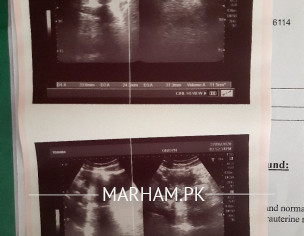

i am 25 years old 5.8 inches tall unmarried weighing 71 kgs. My mother and maternal grandmother had cyst issues my mother also have hyperthyroidism. in last dec my date was 13 but till 23 i didn't bleed. i visited a gynecologist in society she told me i have pcos and right ovary is typical polycystic. she prescribed primolute n for periods for 5 days but i bleeded on 24. ever since then my periods are regular. recently i had my periods on 29th day of my cycle. but this time i only bleeded for 2 days, on 3rd day very little blood was seen on washing , pad remained unstained on 4tg day i had brown discharge. i never had very heay bleeding ever but i use to bleed a little on 3rd day too. i had my harmones check in January they all are normal. today i visited a gynecologist in ultrasound my right ovary appeared large and bulky. she prescribed me folic acid n said yet the issue is not severe but can be in future and asked me to take folic acid every day and notice my cycle for 2-3 months.

mam with due respect ultrasound report is attached above.. have a look and suggest .

in pco there should b bilateral polycystic u dont have pco as such but at border line it could b. dnt worry continue folic acid one daily and try for normal conception